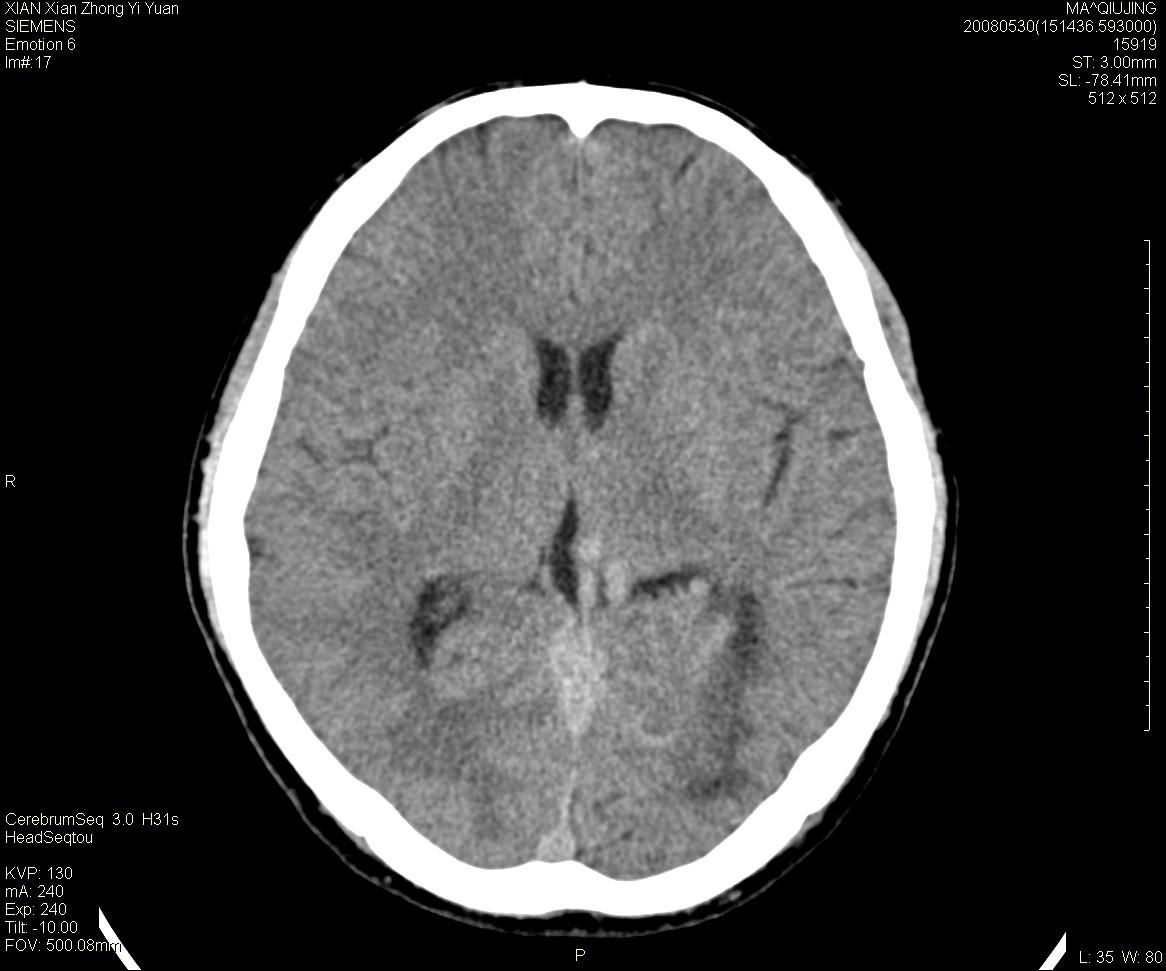

标题: CT13768:少见病例,血管畸形。

患者m47,头晕数年,没给强化,让做dsa去了。

avm

第一感觉:avm,但其中更低密度区不清楚,好像有脂肪密度,胆脂瘤破裂?

avm,低密度区应该是以前出血过的液化灶

血管畸形,支持,如果增强扫描,则可见粗大,迂曲血管团。